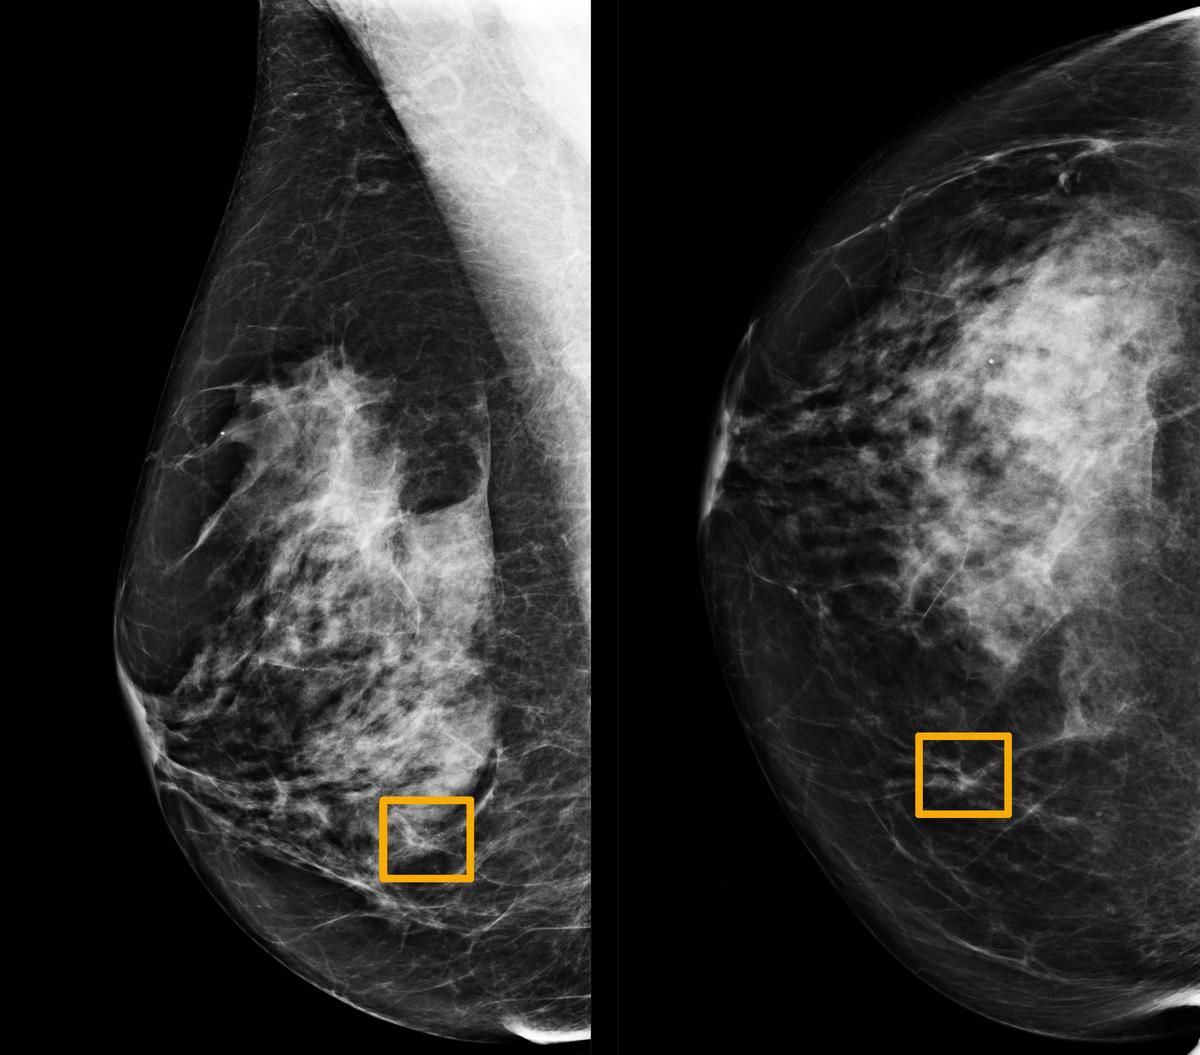

🎗 Artificiell Intelligens ökar träffsäkerheten vid diagnos av bröstcancer

Ett AI-system ger lika bra eller bättre resultat än radiologer vid upptäkt av bröstcancer vid analys av mammogram.